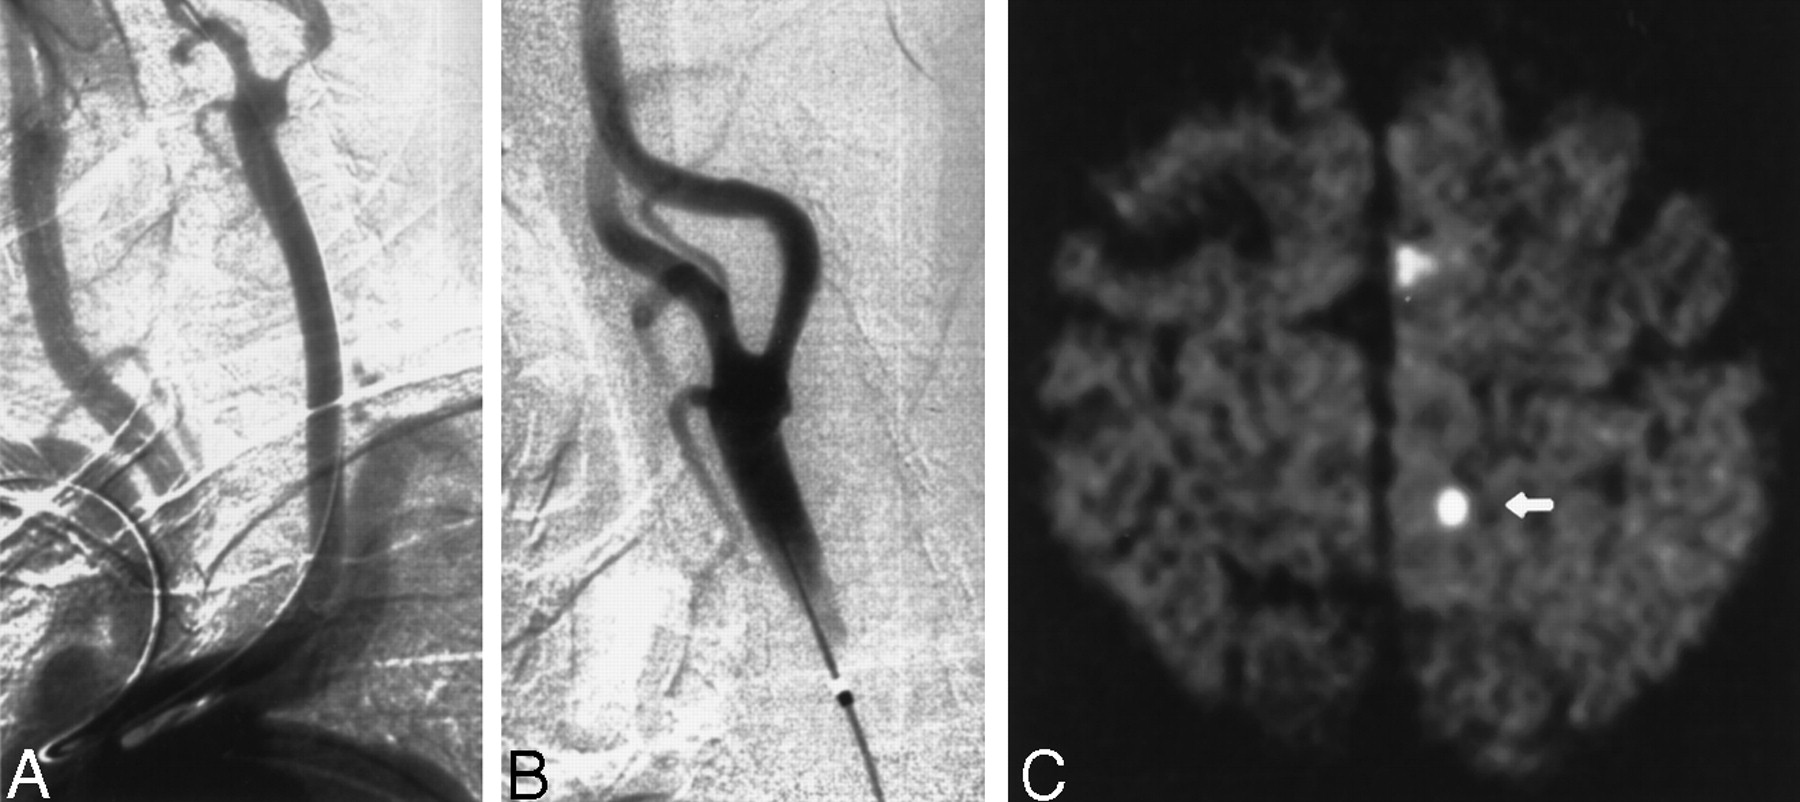

Images obtained in a 86-year-old man with a symptomatic stenosis of the carotid artery.

A, Left anterior oblique angiogram (transbrachial approach) shows an 87% stenosis of the left ICA.

B, Left anterior oblique angiogram shows the result after stent implantation.

C, Postprocedural axial diffusion-weighted MR image (6000/103/1) shows six new ipsilateral lesions (5–10 mm) in the cortical territory of the ACA (arrow).